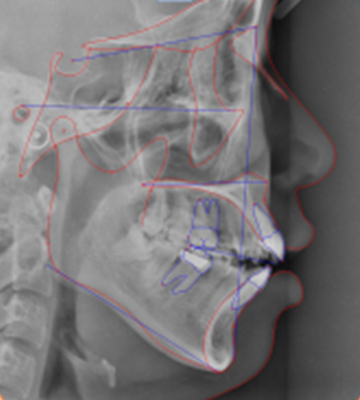

3차원 치과 CT 및 Pano.

수완부 촬영을 통해 성장예측까지 진단하여 정밀진단을 시행합니다.

국내 최고의 교정진단 소프트웨어를 통해 정확한 계측 및 예상되는 결과를 제공합니다.

국립부산학교치과병원 치과교정과와 동일한 치료철학을 가지고, 동일한 교정분석법으로

분석하고, 치료계획을 세웁니다.